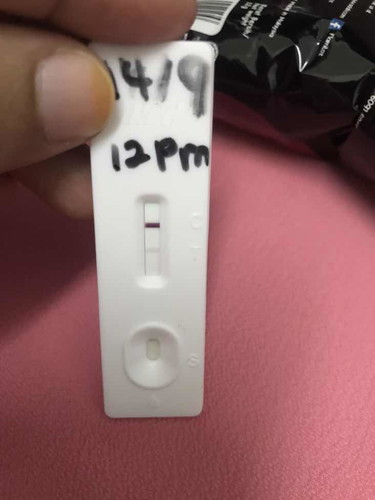

Positif selepas keguguran

Sy keguguran pada 15/7/2022 . Tapi hari ni check tiba-tiba naik 2 line . Betul pregnant ke or hormon pregnancy lama ?

pregnancy lama akan hilang dalam tempoh sebulan 🤗 lebih dari tu cuma sesetengah je . kalau nak confirmation, check je upt lain. saya masa nak confirmkan pregnancy semula after keguguran pun saya test 2 3 kali berbeza hari & ada yang hari sama 🤗